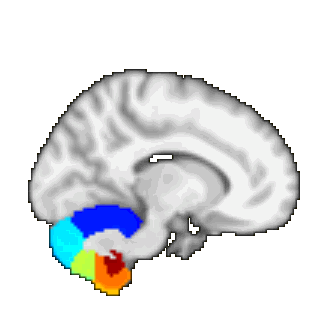

Oxford thalamic connectivity atlas

A probabilistic atlas of 7 sub-thalamic regions, segmented according to their white-matter connectivity to cortical areas, kindly provided by Heidi Johansen-Berg and Timothy Behrens, FMRIB.

This connectivity atlas reports probability of anatomical connection from points in the thalamus to each of 7 cortical zones. These probabilties are calculated using probabilistic diffusion tractography in multiple subjects. For more details see the Thalamic Connectivity Atlas web page.